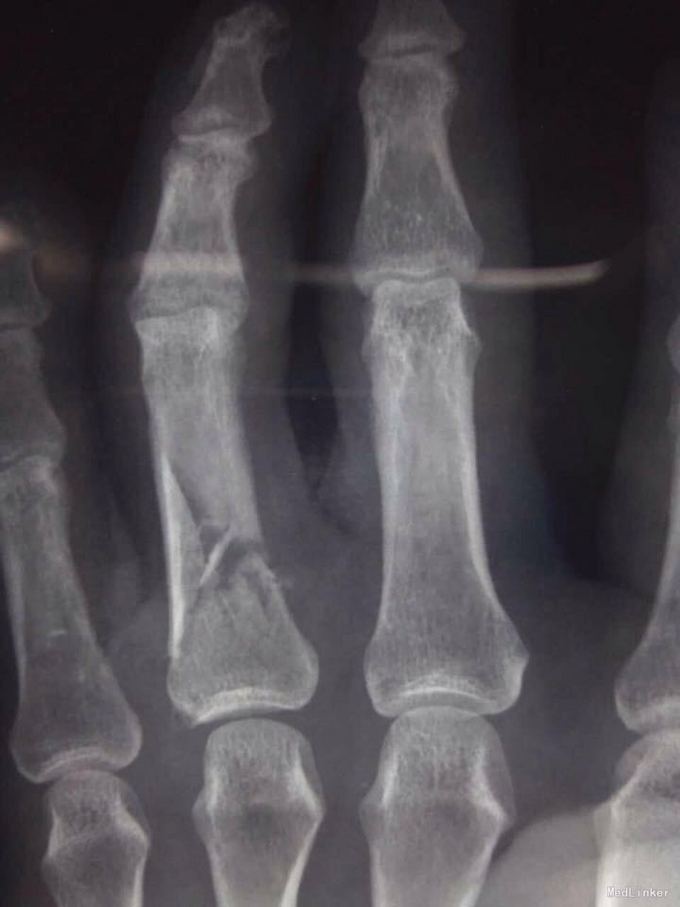

电锯伤致手流血疼痛

环指开放性骨折,肌腱断裂

环指开放性骨折 伸指肌腱断裂 予以清创缝合 指骨骨折克斯针内固定 肌腱修复